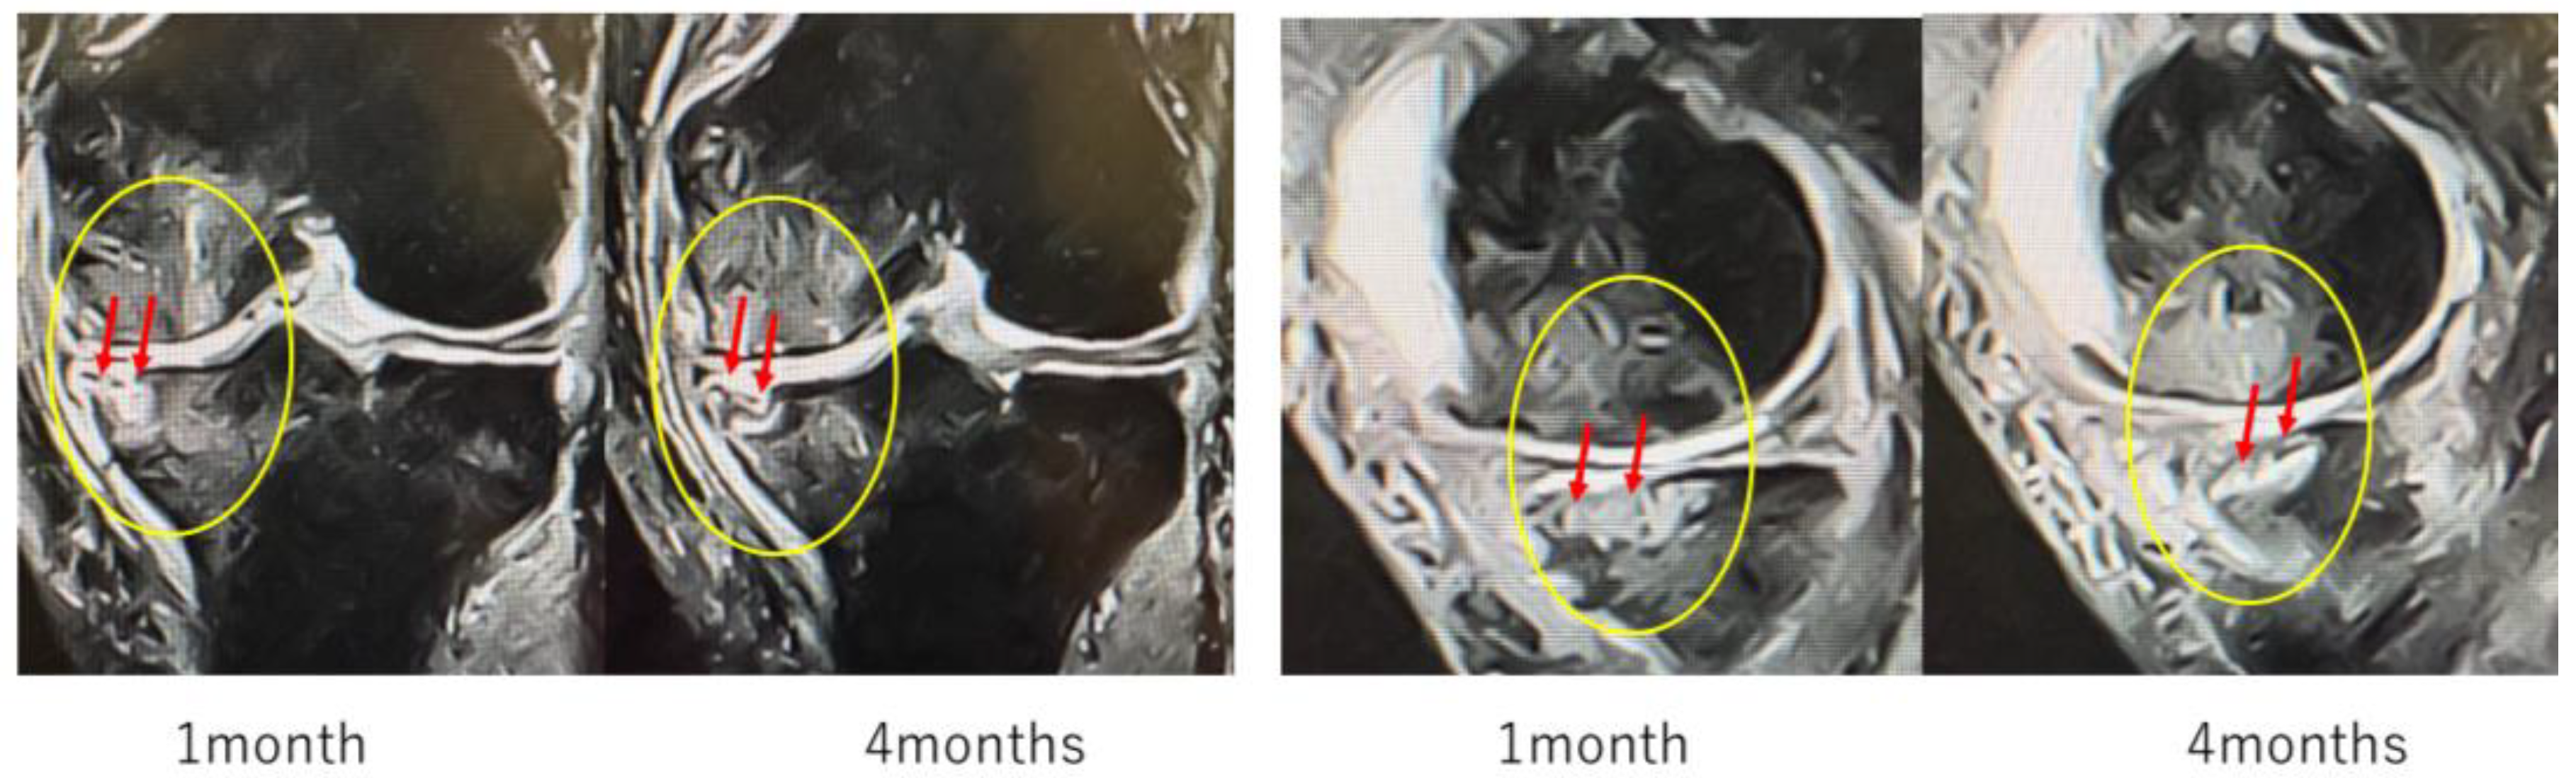

Case Reports

In Case 3 (Figure 8), a 70-year-old male, at baseline, MRI revealed the disappearance of the cartilage layer and SBP tear associated with a BML in the medial femoral condyle and tibial plateau. At 1-month post-treatment, mosaic-like high-signal areas extended throughout the region surrounding the BML. At 4 months, the mosaic-like areas and a reduction in BML were observed. At 7 months, although no improvement in the cartilage layer was detected, areas of bone sclerosis had expanded to cover the joint surface, indicating progression of bone repair. It was considered that the repair process was still in progress.

Figure 8.

Temporal MRI changes after treatment. At baseline, a BML with cartilage layer loss and SBP tear was observed in the medial femoral condyle and tibial plateau. At 1 month, mosaic-like high-signal areas spread around the BML. At 4 months, BML reduction and mosaic-like changes were seen. At 7 months, no cartilage recovery was evident, but bone sclerosis expanded to cover the joint surface.

Figure 10 (Case 5) shows T2-weighted MRI findings at 1 and 4 months after intraosseous MSC administration. In sagittal and coronal views, progressive subchondral bone collapse and depression of the articular surface were observed, which became more pronounced between 1 and 4 months. These morphological changes were accompanied by alterations in joint congruity, suggesting ongoing structural compromise that may predispose to secondary osteoarthritic changes.

Figure 10.

Progression of subchondral bone collapse after intraosseous MSC administration (T2-weighted images). MRI scans at 1 month and 4 months post-treatment. The left images show sagittal views, and the right images show coronal views. Yellow circles and red arrows indicate progressive subchondral bone collapse and depression of the articular surface from 1–4 months. In cases with extensive BML near the articular surface, MSC administration may increase bone fragility, necessitating cautious rehabilitation and load management.

Particularly in cases with extensive BML located adjacent to the articular surface, MSC administration may increase bone fragility, indicating the need for careful rehabilitation and load management.